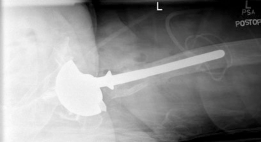

--- Fig. 20.13 Cross-table lateral hip radiograph—revision THA components with appropriate anteversion